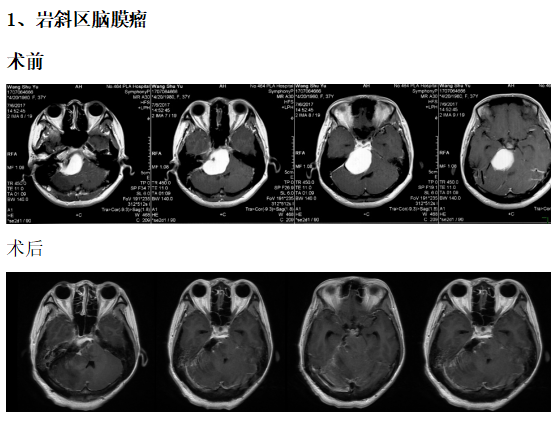

典型病例介绍